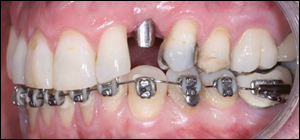

Fig 2: Braces were placed on the lower cuspid in an attempt to intrude it. Intruding a lower cuspid is difficult to do because of the inherently long root on lower cuspids and the dense bone of the mandible